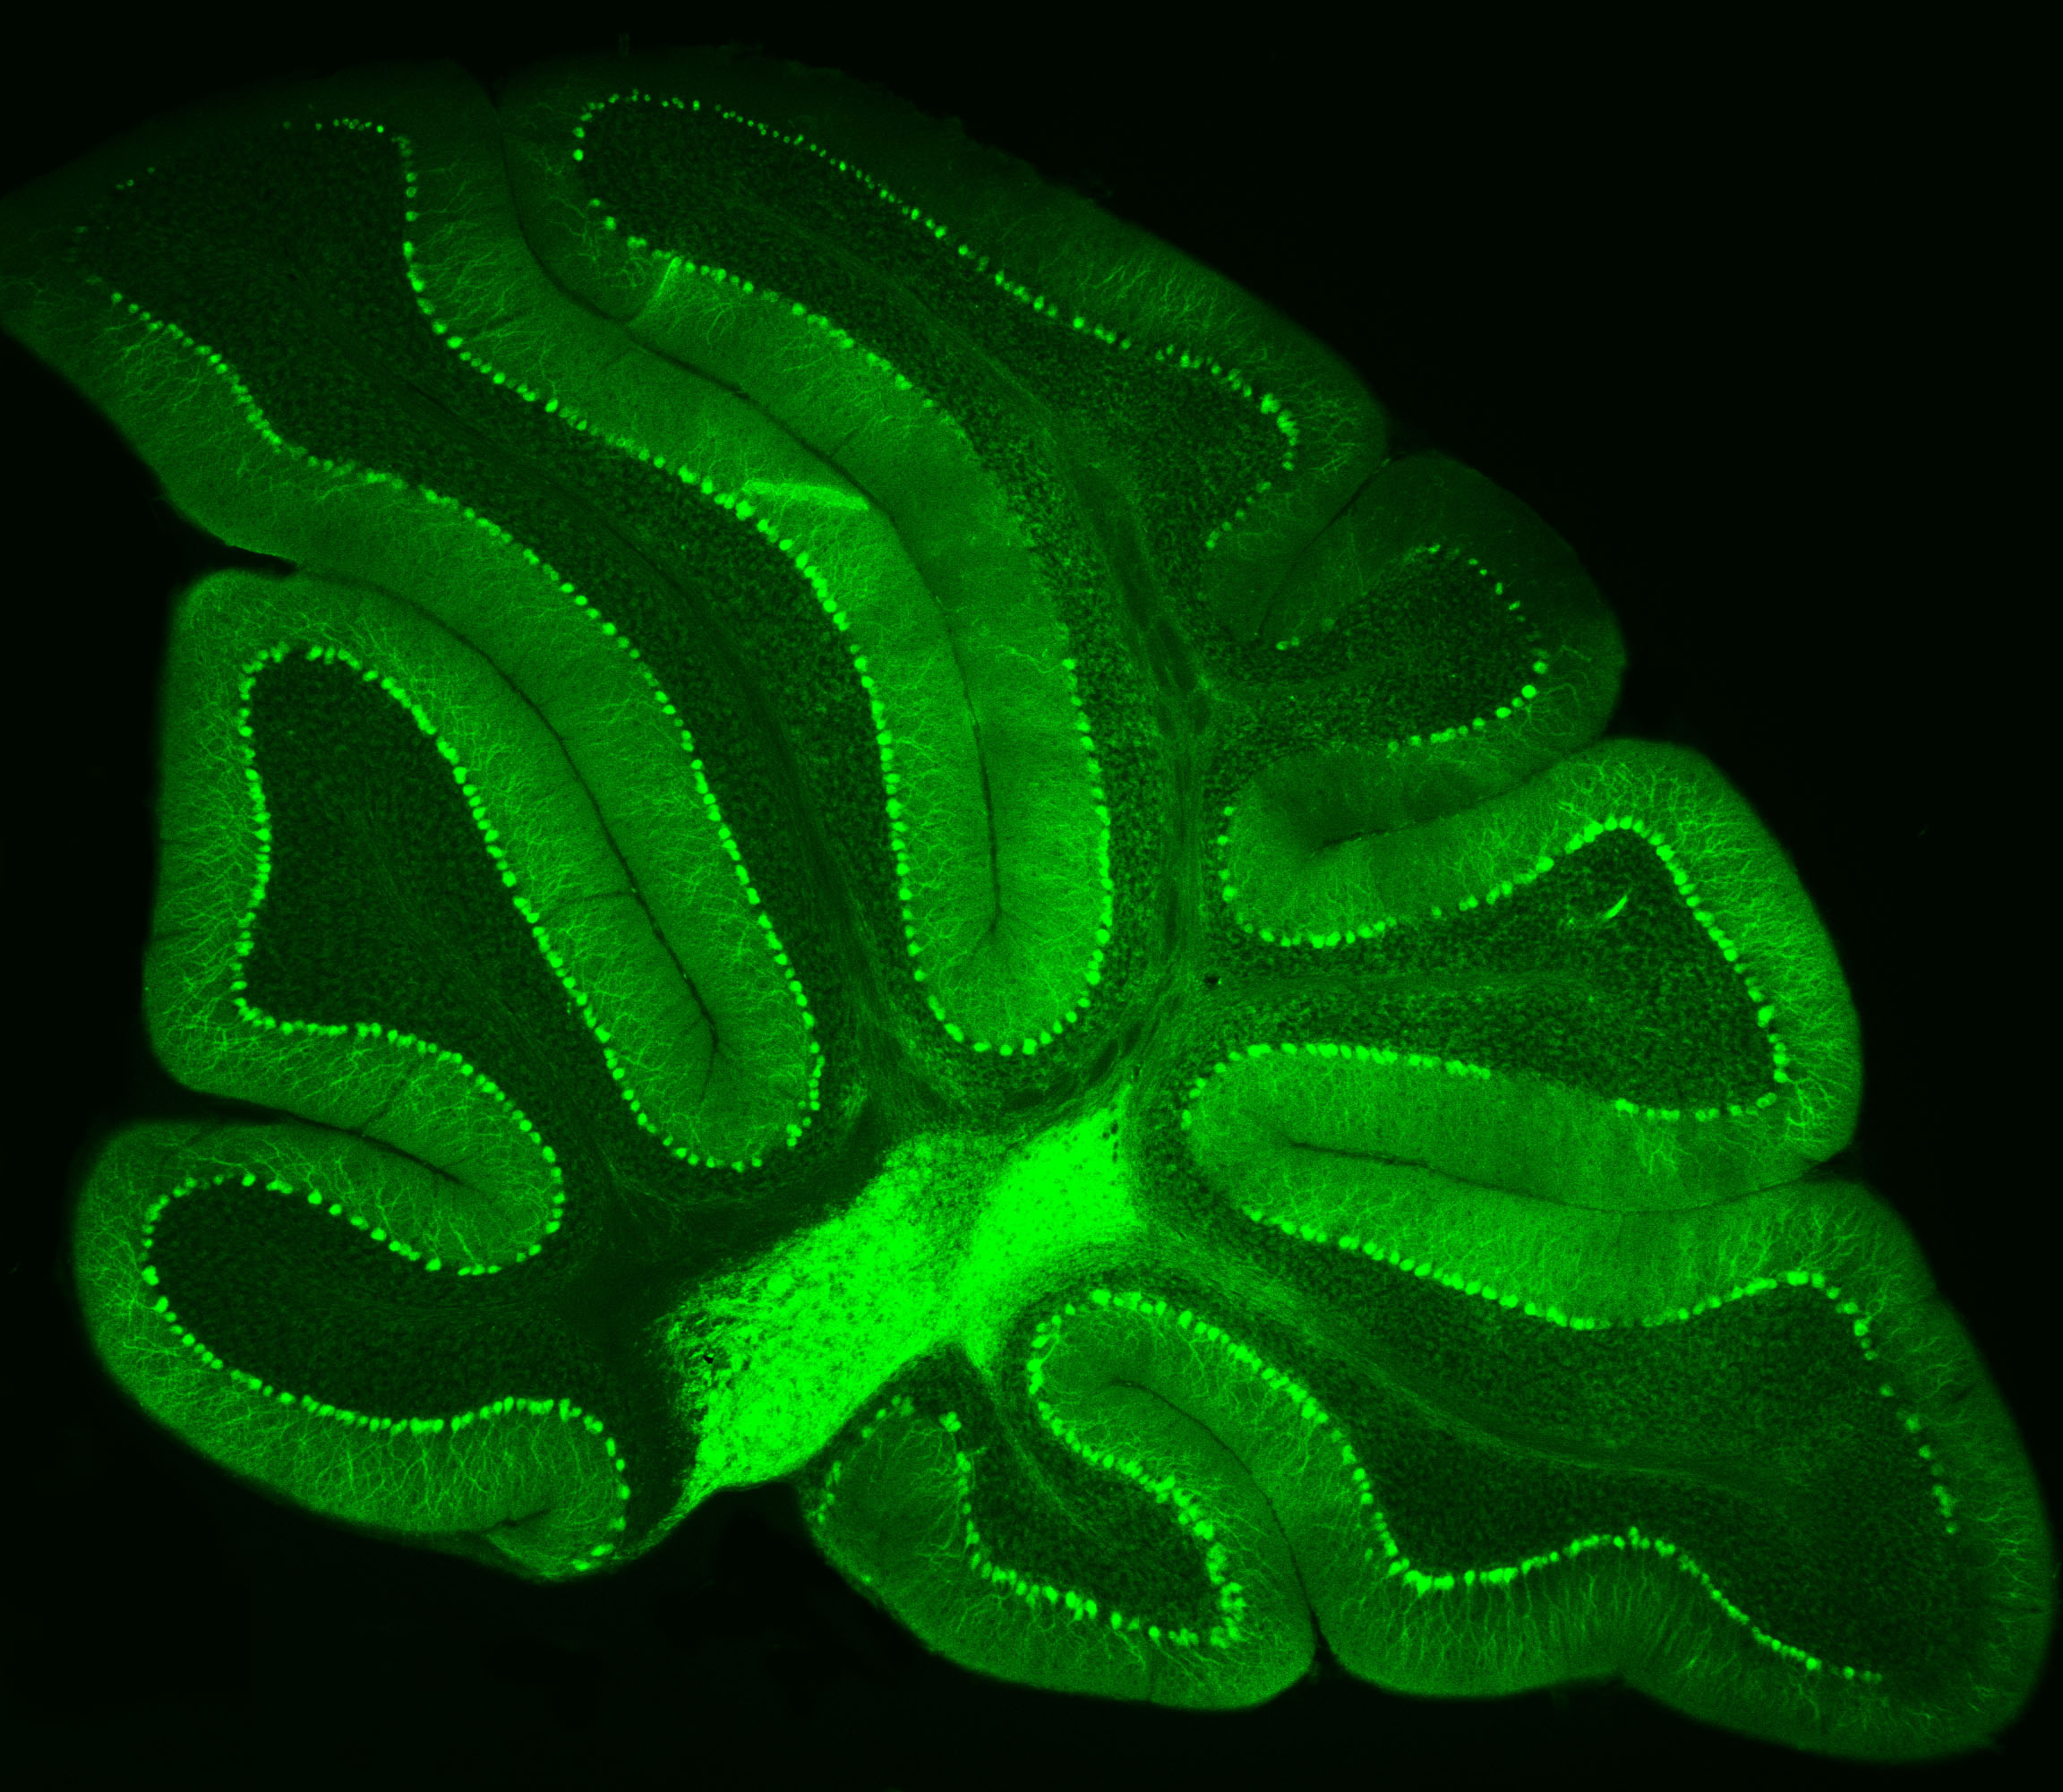

Neurons in Green

Purkinje neurons from an animal model are labeled with green fluorescent protein (GFP), which causes them to glow bright green.

– Credit: Pennington Biomedical

At Pennington Biomedical Research Center, scientists often study the brain by highlighting specific cells so they can be seen more clearly under a microscope. This technique was recently used by Dr. Yanlin He, associate professor and director of the Brain Glycemic and Metabolism Control Laboratory, who is examining Purkinje neurons in the cerebellum.

Purkinje neurons are best known for helping control movement and motor learning, but researchers are discovering they may have other important roles in the body as well, such as controlling energy balance and blood sugar.

By making these neurons glow green, Dr. He and his team can see their complex branching shapes and how they connect within the cerebellum’s neural network.

This technique also allows researchers to perform electrophysiology recordings, which measure the electrical activity of the cells in a laboratory setting. Their work could help scientists better understand how the brain helps regulate metabolism and overall health.